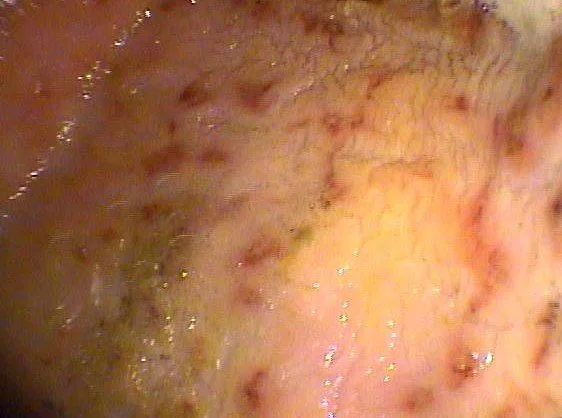

Grade 4 Squamous Ulcers

Epona Equine has a 3.2m Gastroscope available for diagnosis of Equine Gastric Ulcer Syndrome. We can diagnose both squamous and glandular ulcers in the stomach. Scoping is the only way to definitively diagnose ulcers in horses.